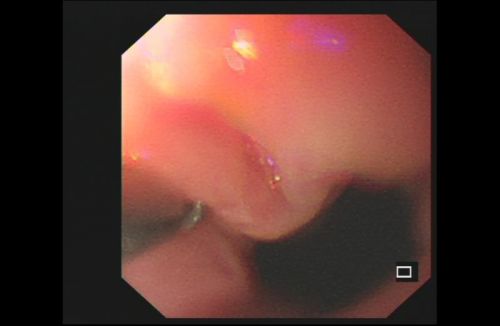

再次胃镜检查发现食管下段近贲门处有一个小洞,磁力珠可能就是从这里进入黏膜下层。

赶紧再进行胃镜检查,然而,在胃腔、食管内并未发现残余的珠子。又做了X光检查,这才发现2颗漏网之珠紧密吸附在胃与贲门的位置。再次胃镜发现,在食管靠近贲门和胃底靠近贲门处各有一个洞,2颗磁珠应该是相互吸引嵌入粘膜下组织“藏”了起来,所以未被发现。